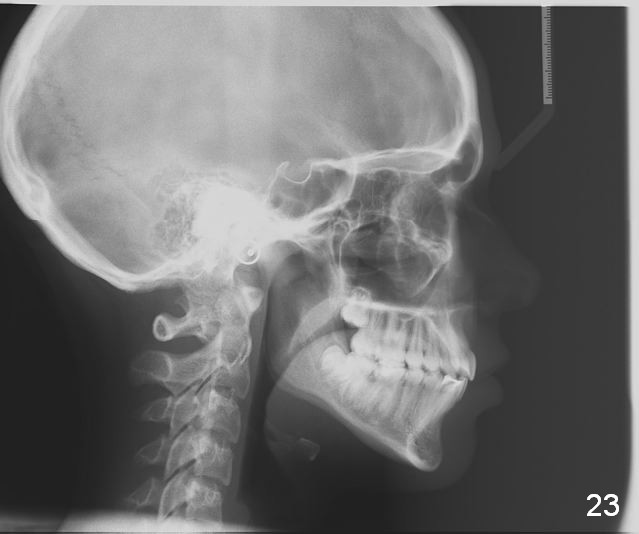

Final Results of Unilateral Class II Malocclusion

After using Rapid Molar Distalizer.  Total treatment lasts 50 months.